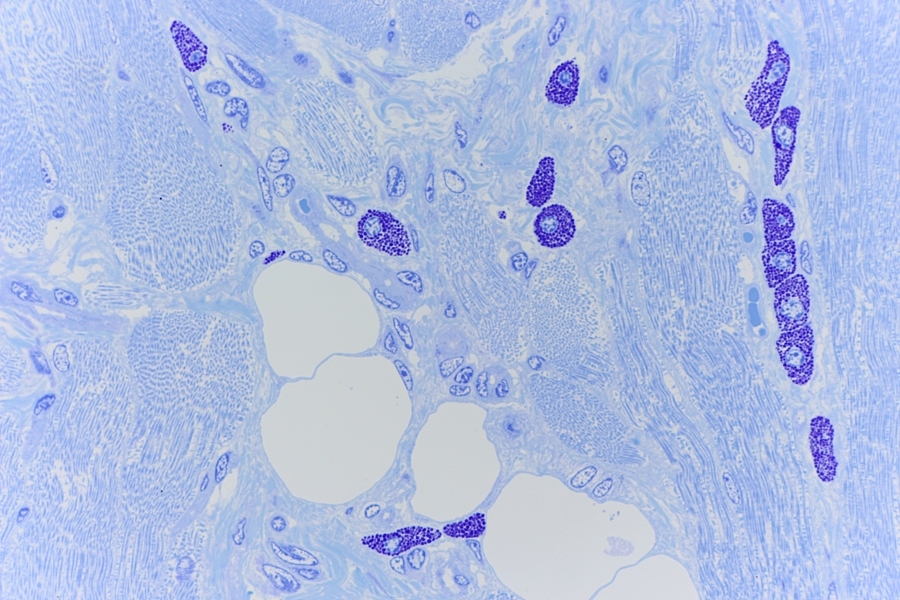

Mestcellen zijn ovale tot ronde cellen met een doorsnede van 20-30µm, waarvan het cytoplasma rijkelijk gevuld is met basofiele granula. De centrale, ronde kern gaat bij bestudering in een lichtmicroscoop vaak schuil achter de granula. In een coupe vervaardigd uit paraffine zijn de afzonderlijke granulaatkorrels en celkern vaak minder goed zichtbaar. In een coupe van kunststof zoals Technovit of Epon is de coupedikte zo gering dat de mestcel meestal wel met granulaat en kern duidelijk zichtbaar kan worden gemaakt. Zie afbeeldingen op de website (Red).

Mestcellen zijn tamelijk lang levende cellen en zijn, in tegenstelling tot de andere vaste bindweefselcellen, waarschijnlijk afkomstig van een stamcel[2] in het beenmerg[2]. De cel komt door het hele lichaam voor, maar vooral in de dermis[2] (rond de bloedvaten), het darmkanaal en de luchtwegen. De cellen kunnen zichtbaar gemaakt worden door een metachromatische kleurreactie[3], waarin toluidineblauw de granula roodachtig purper kleurt, doordat zij gesulfateerde glycosaminoglycanen[2] bevatten.

Mestcellen in een muizen tong preparaat

In de hier getoonde coupes van een muistong zijn geen mestcel ophopingen te zien maar wel zijn de mestcellen in grote hoeveelheden aanwezig. In bijvoorbeeld menselijk weefsel komen veel minder mestcellen voor[Red].

In ‘A practical guide to the histology of the mouse’ is te lezen dat bij knaagdieren deze grote hoeveelheid volledig normaal is en dus geen

ziektebeeld is. Citaat: “Heavily granulated mast cells are commonly seen in normal rodent tongues and can be demonstrated with toluidine blue staining.”[5]